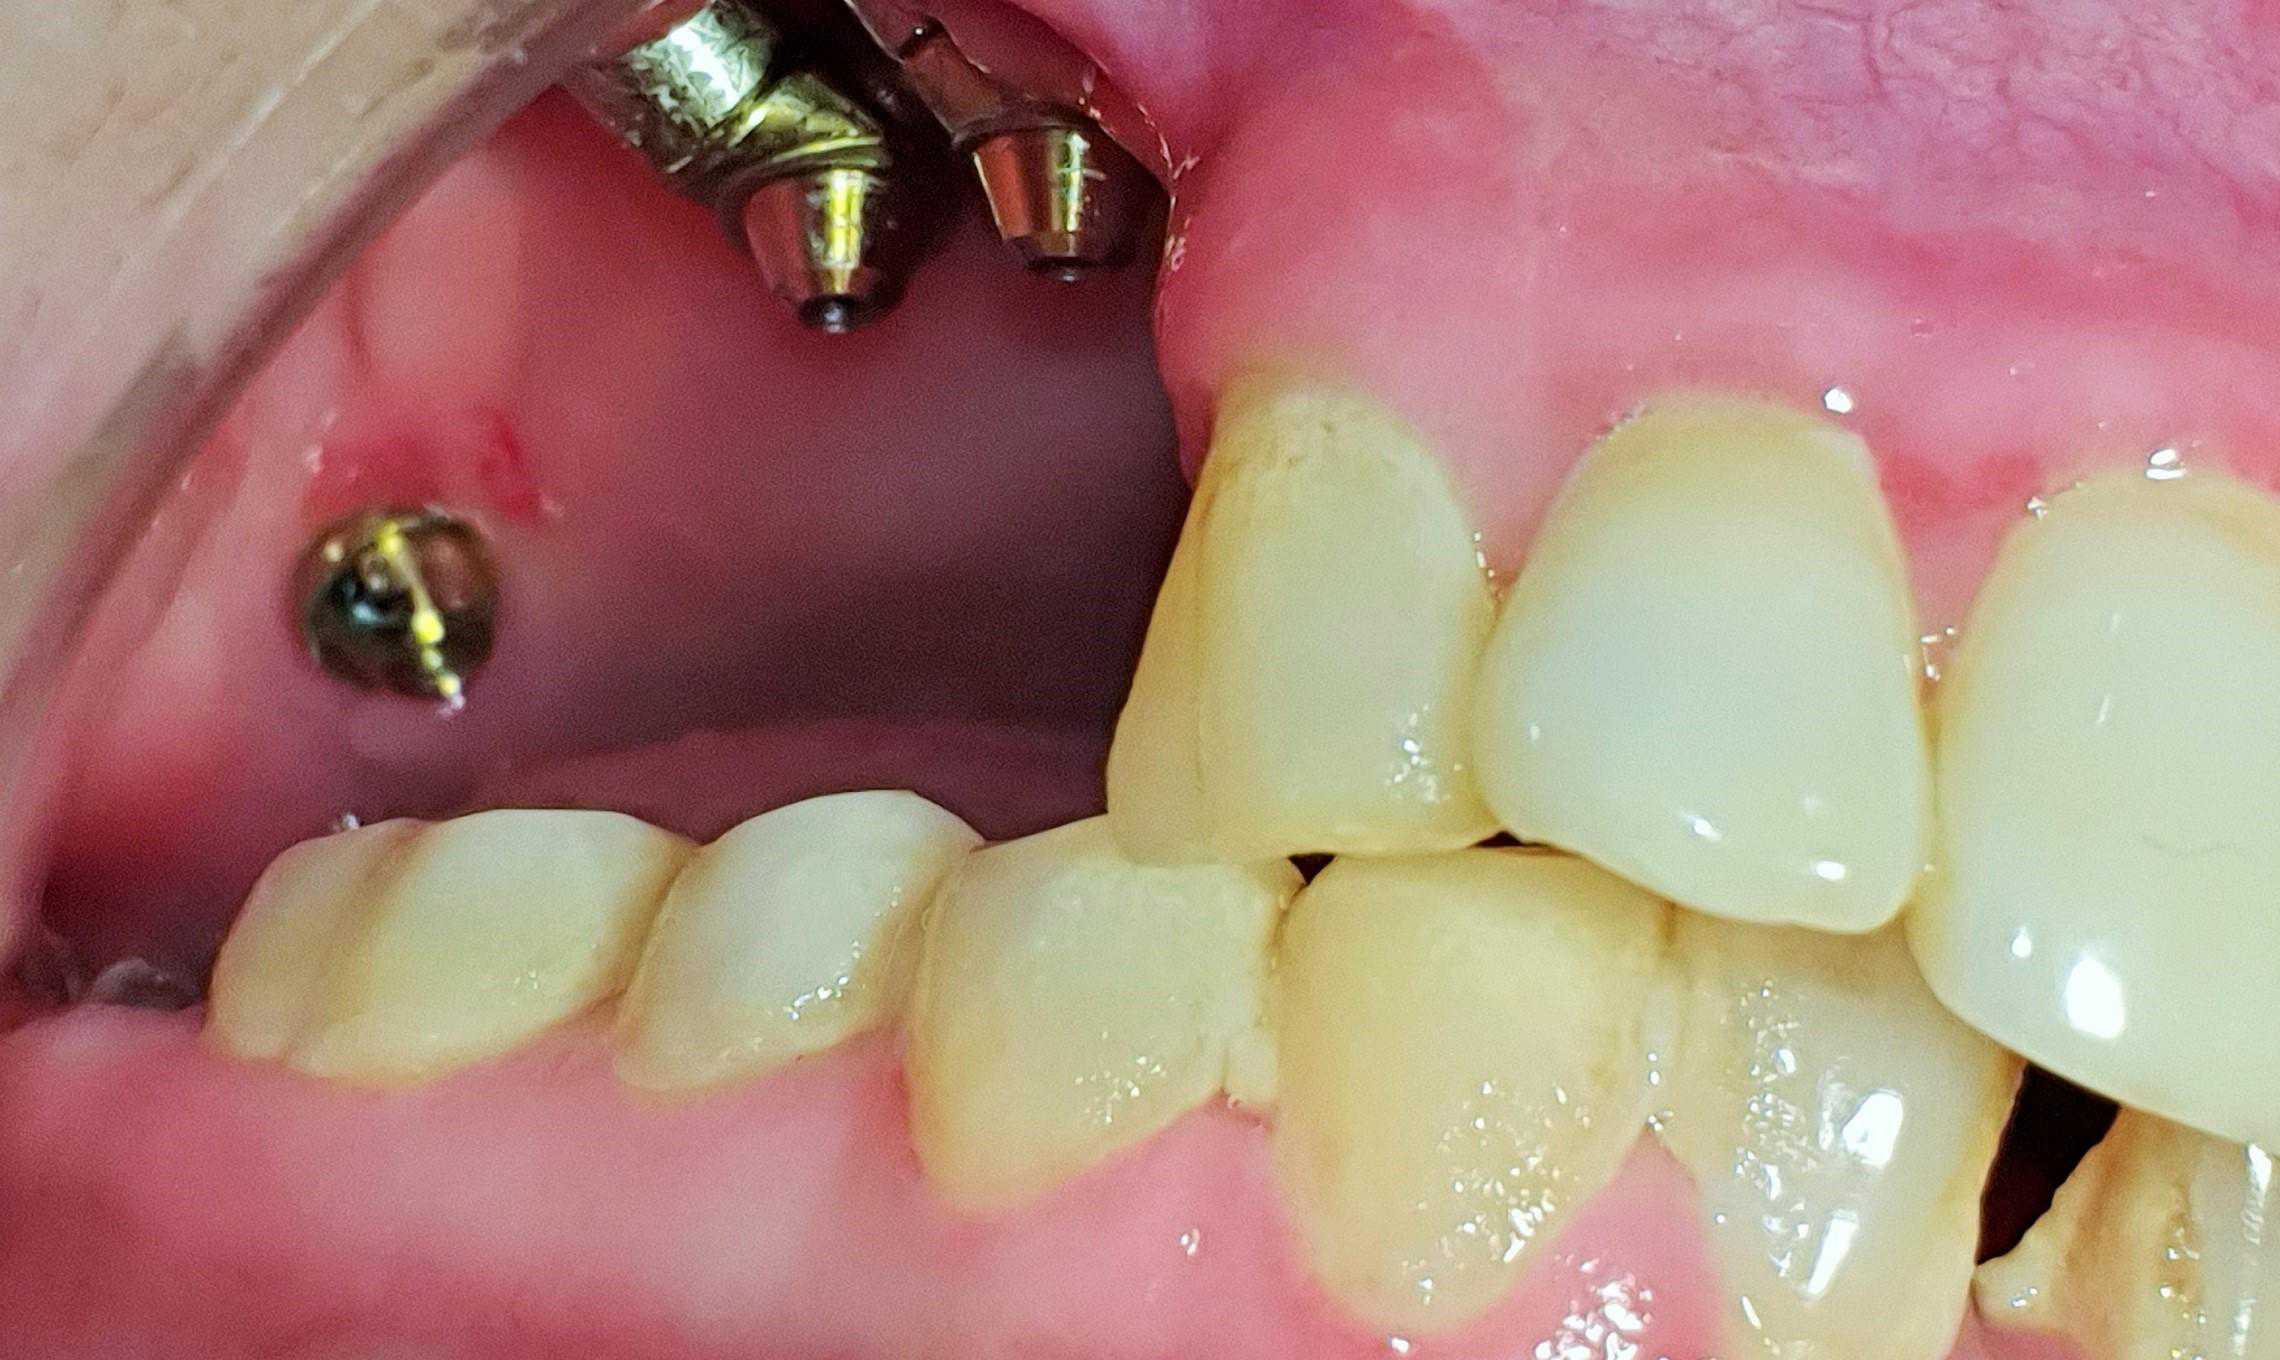

https://demo.discussdentistry.com/forums/topic/post-mucormycosis-avascular-necrosis-of-maxilla-rehabilitation-with-zygomatic/#post-24499 <![CDATA[Post Mucormycosis Avascular necrosis of maxilla, rehabilitation with Zygomatic]]> https://demo.discussdentistry.com/forums/topic/post-mucormycosis-avascular-necrosis-of-maxilla-rehabilitation-with-zygomatic/#post-24499 Thu, 25 Aug 2022 12:14:40 +0000 Sankalp Mittal

• 20210604_101325 (2)20210604_101317 (2)20210604_103315 (2)20210604_102857 (2)20210604_104202 (2)20210604_104853 (2)20210824_105656 (2)20210824_112353 (2)20210824_114957 (2)20210824_131302 (2)20210826_100648 (2)20210826_100749 (2)20210826_100919 (2)20210914_183943 (2)20211001_17535220211012_18543620211012_192043 (2)20211012_185627 (2)20211012_195430 (3)20211027_193725 (2)20211027_200729 (2)20211027_200919